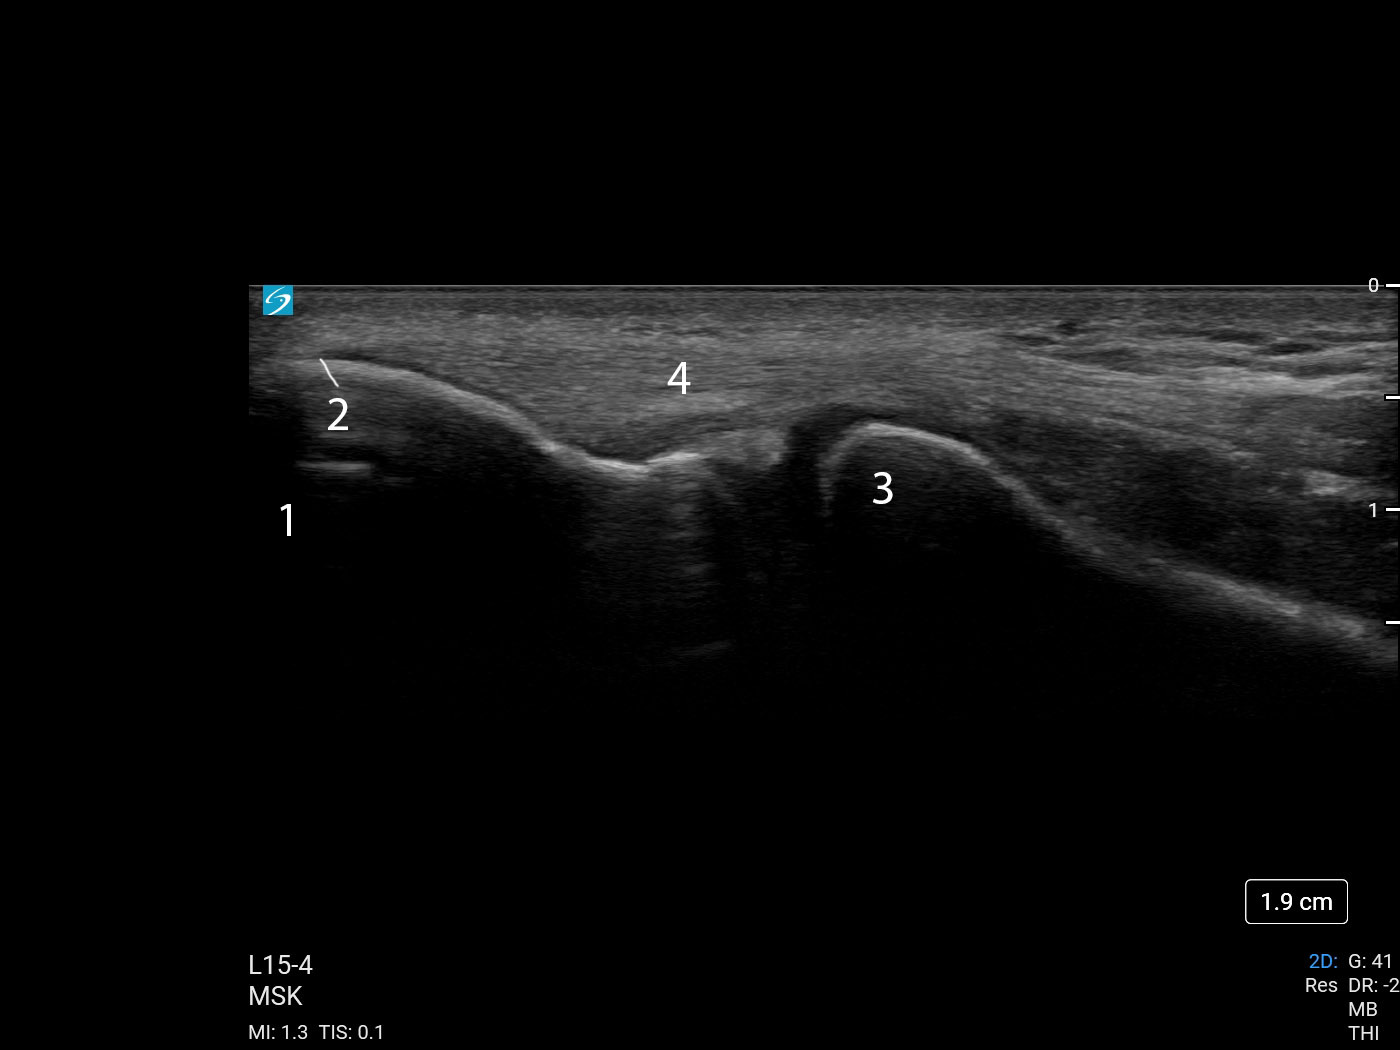

肘外側上顆の解剖1の画像

外側上顆

腱の挿入

橈骨頭

総伸筋腱

星印:トランスデューサービームの場所